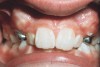

Figure 10  On completion of treatment, good posterior occlusion was attained.

Figure 10

Figure 11  At age 14 and completion of full appliance therapy, the patient’s facial changes were dramatic. A balanced profile with excellent lip support was achieved.

Figure 11